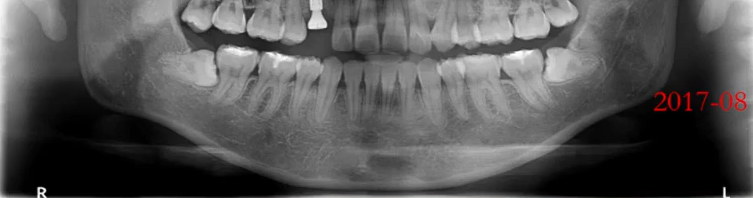

【病例2】

张XX,女,34岁

曲面断层片怎么看口腔精读 | 一次性教你看懂曲面断层片!_https://www.jmylbn.com_新闻资讯_第29张

1、牙槽骨水平性吸收,个别有垂直性吸收

2、全口结石影

治疗:洁刮治

检查:牙周探诊、咬合检查

正畸治疗考虑及设计

曲面断层片怎么看口腔精读 | 一次性教你看懂曲面断层片!_https://www.jmylbn.com_新闻资讯_第30张

3、牙缺失

治疗:种植治疗

检查:CBCT,对合牙

牙周治疗及维护

曲面断层片怎么看口腔精读 | 一次性教你看懂曲面断层片!_https://www.jmylbn.com_新闻资讯_第31张

4、智齿阻生

治疗:拔除

检查:颌骨评估、阻生齿评估、邻牙评估

曲面断层片怎么看口腔精读 | 一次性教你看懂曲面断层片!_https://www.jmylbn.com_新闻资讯_第32张

5、根尖周炎

治疗:根管治疗,冠修复

检查:CBCT,根管及牙槽骨评估;临床,桩核冠修复条件。